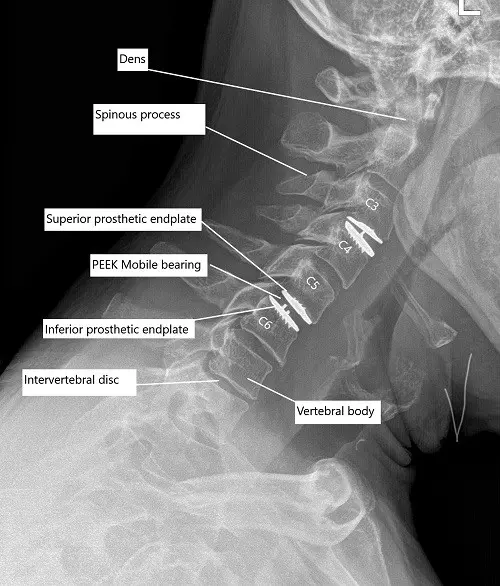

Post-op x-ray of the cervical spine showing total cervical disc replacement at C3-C4 and C5-C6 level

- Total disc arthroplasty cervical using Mobi-C 15 mm x 15 mm x 5 at C3-4.

- Total disc arthroplasty cervical using Mobi-C 17 mm x 15 mm x 6 mm at C5-6.